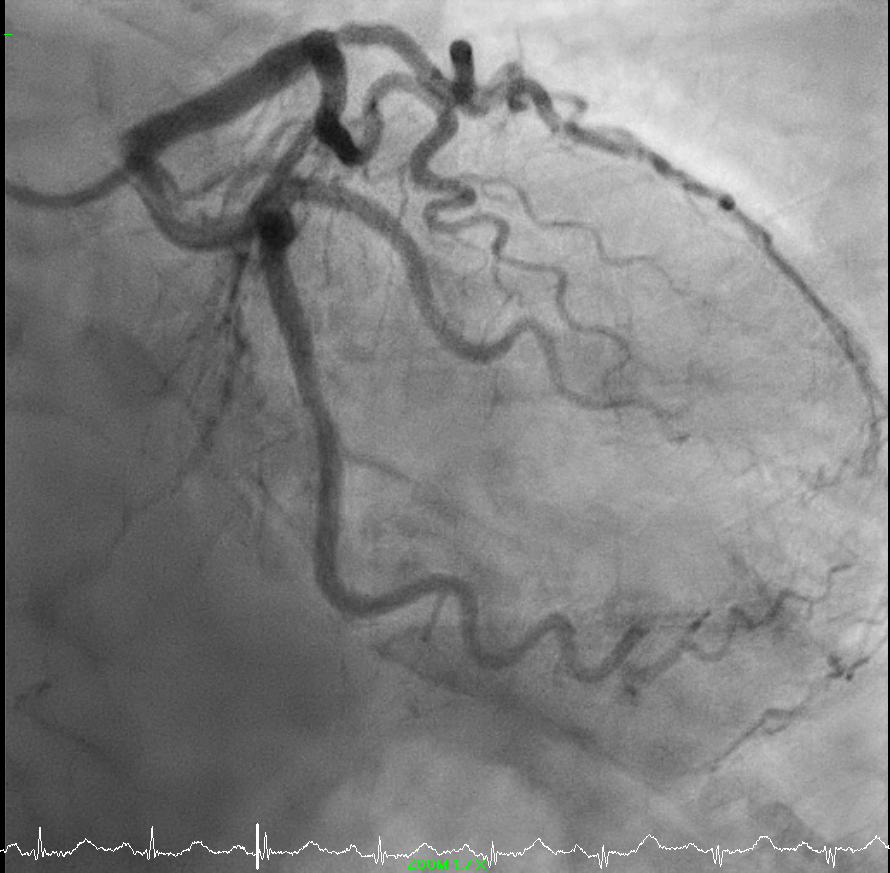

Coronary angiography showed complete total occlusion of right posterior left ventricular branch with collaterals from left system and moderate disease of first diagonal.

Right radial pulse was not strong. Ultrasound revealed a small right radial artery. Decided for left radial artery approach. Single puncture successful with ultrasound guidance. Optitorque 5FR catheter. Left coronary angiogram images obtained.